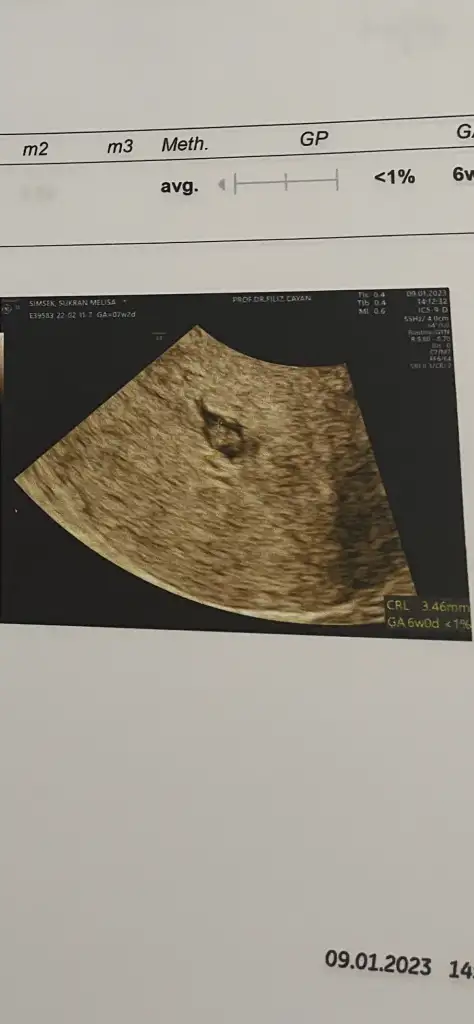

Merhaba 7+3 haftalık alttan ultrason görüntümüz içimize hep erkek doğuyor ama Allah en güzelini verir :)

Banada tahminde bulunur musunuz lutfeen 8+3 ultrasonda karından ultrason bu arada